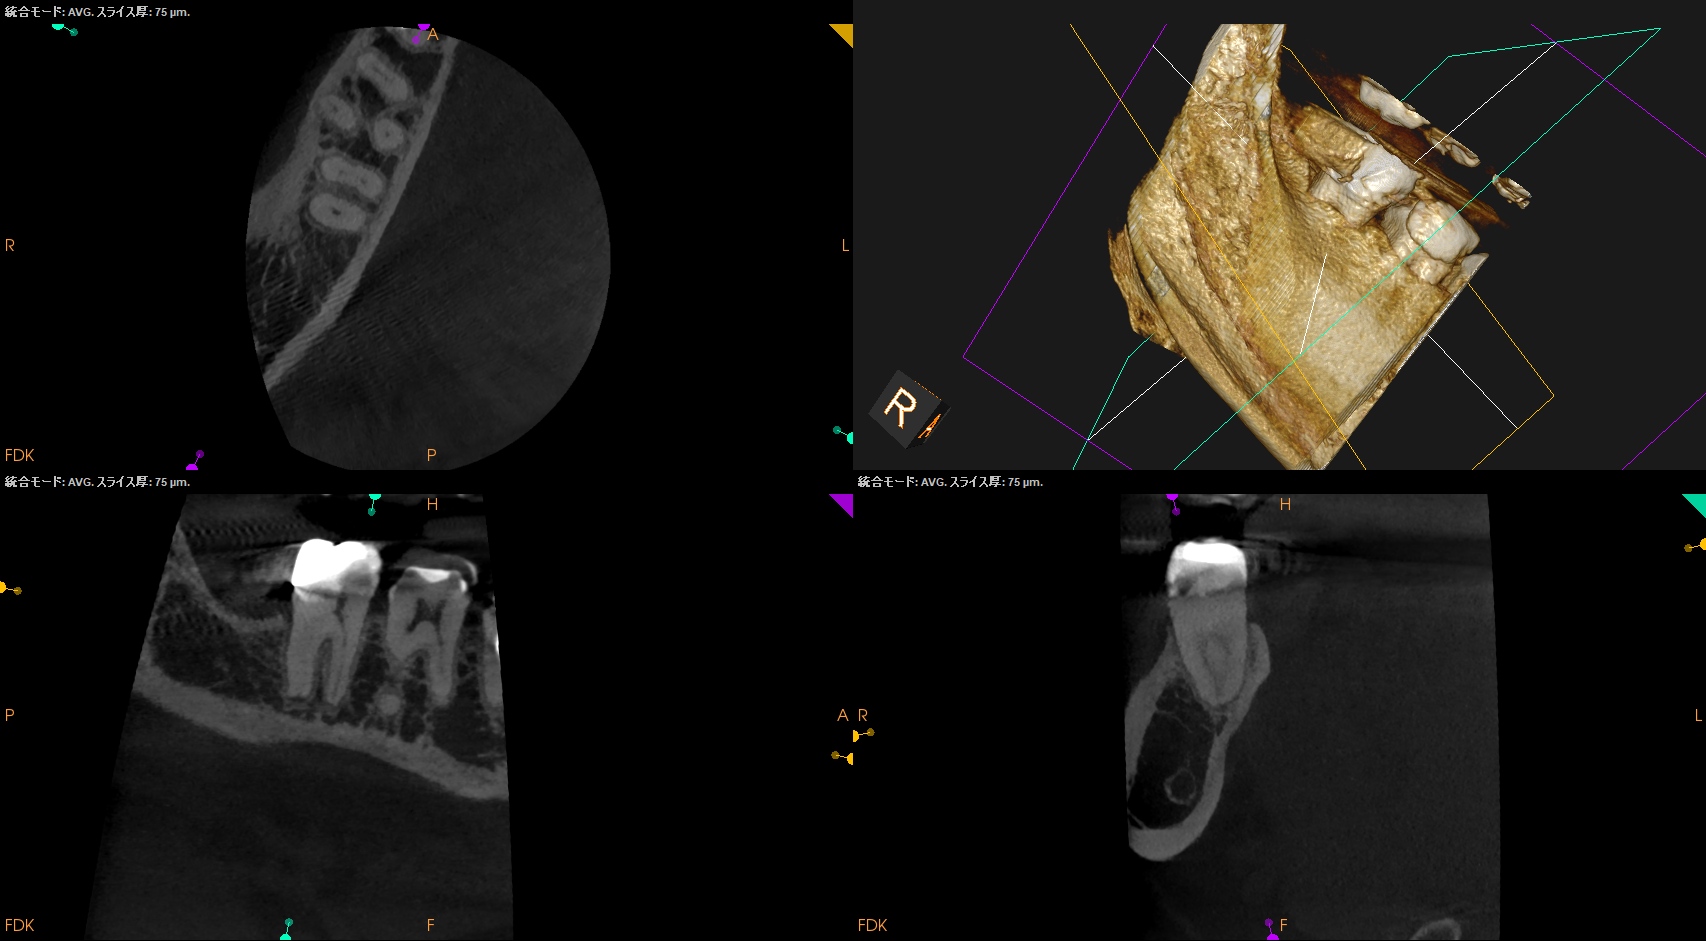

以下のように根管形成した。

Dは#60.02で形成しても出血がペーパーポイントに見られたためにProTaper Gold F5まで形成した。

ML,MBは合流していることが多いと言う解剖学的情報をもとに以下のように合流部分をチェックした。

問題はないだろう。